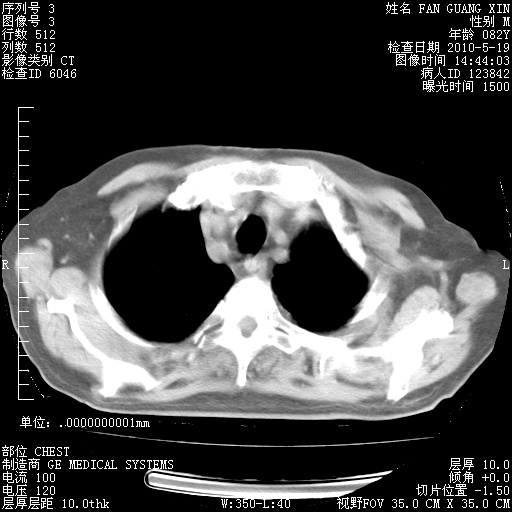

可改为口服强的松40-50mg/d治疗,若病情仍稳定,胸部阴影不再吸收可逐渐减量